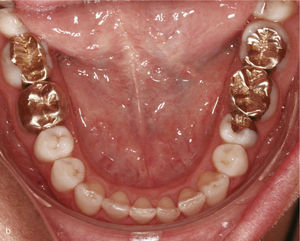

Extracción de dientes anterioresLa falta grave de espacio en el sector anterior hace que en algunos casos sea necesario extraer un diente anterior con el fin de disponer del espacio suficiente para conformar la arcada dentaria y lograr una sobremordida funcional. En la figura 12a se observa la mandíbula de un paciente con falta de espacio en el sector anterior, dientes anteriores rotados y el diente 43 inclinado hacia vestibular. En extracciones realizadas en el sector anteroinferior se colocan sistemáticamente ataches de anclaje en los dientes adyacentes al futuro espacio de extracción. En este caso se colocaron ataches en los dientes 33, 32 y 44, dado que no sólo se cerró el espacio edéntulo, sino que también se realizó una intrusión del sector anteroinferior. La figura 12b muestra el resultado del tratamiento después de la extracción del diente 42 y del cierre del espacio.

Sector anterior de la arcada inferior con dientes rotados y apiñados (a). La conformación de la arcada se realiza mediante la extracción del diente 42 y la colocación de ataches en los dientes 33 a 44. Vista intraoral de la arcada inferior con un aspecto armonioso y el espacio cerrado (b).